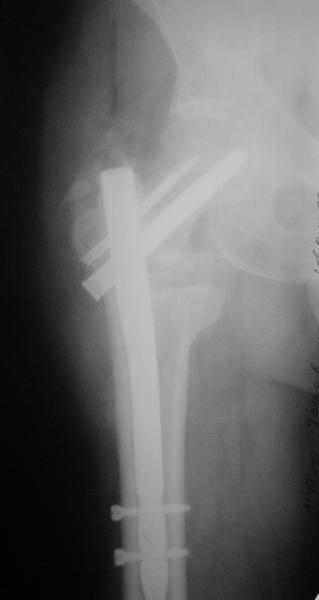

[Ortho] Чрезвертельный перелом бедра

Гвоздем тоже можно, но технически труднее, надо вводить джойстики в шейку...

В приложении пример с гвоздем.